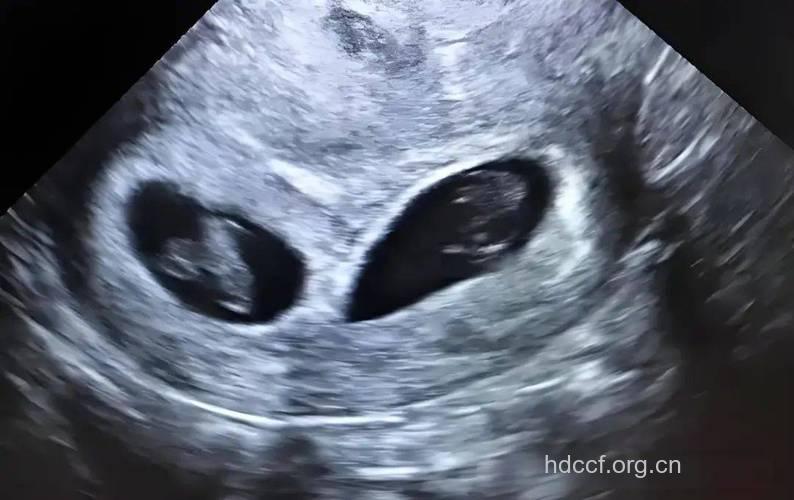

两个宝宝都长眉毛了,为乳牙和恒齿打基础的牙蕾已经长好,孩子的味蕾可能也发挥作用了。不管出生后是什么颜色,他们的皮肤现在都是红红的,皱皱巴巴的。